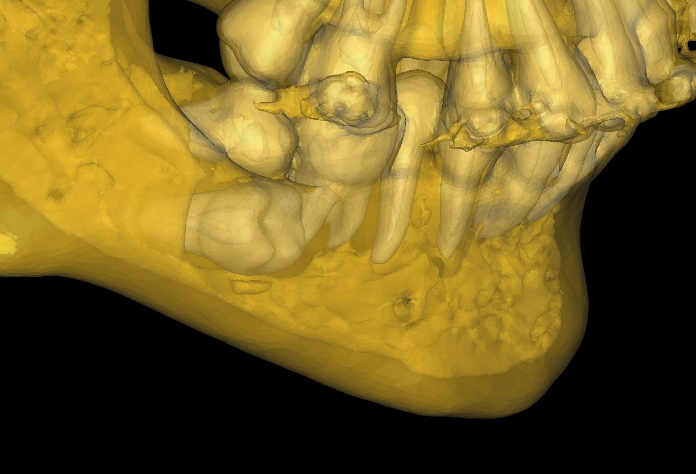

顎変形症とは、極端な上下顎骨の位置異常によるもので、歯科矯正治療単独では治療が困難な疾患です。症状としては摂食障害、発音障害、審美障害があります。治療は、手術によって上下顎骨を適切な位置に移動し、咬み合わせをつくっていきます。手術前・後には当科と提携している矯正歯科医による歯科矯正治療を行います。当科ではCT検査から手術シミュレーションを行い、手術前に上下顎骨の3Dモデルを作製して実際に位置移動を行って手術が適切にできるかどうか評価し、手術シミュレーションの再現性を確実なものとしています。自費治療による歯科矯正治療に対応した手術(サージェリーファースト)も行っています。

手術シミュレーション

実物大臓器立体モデルによる手術シミュレーション